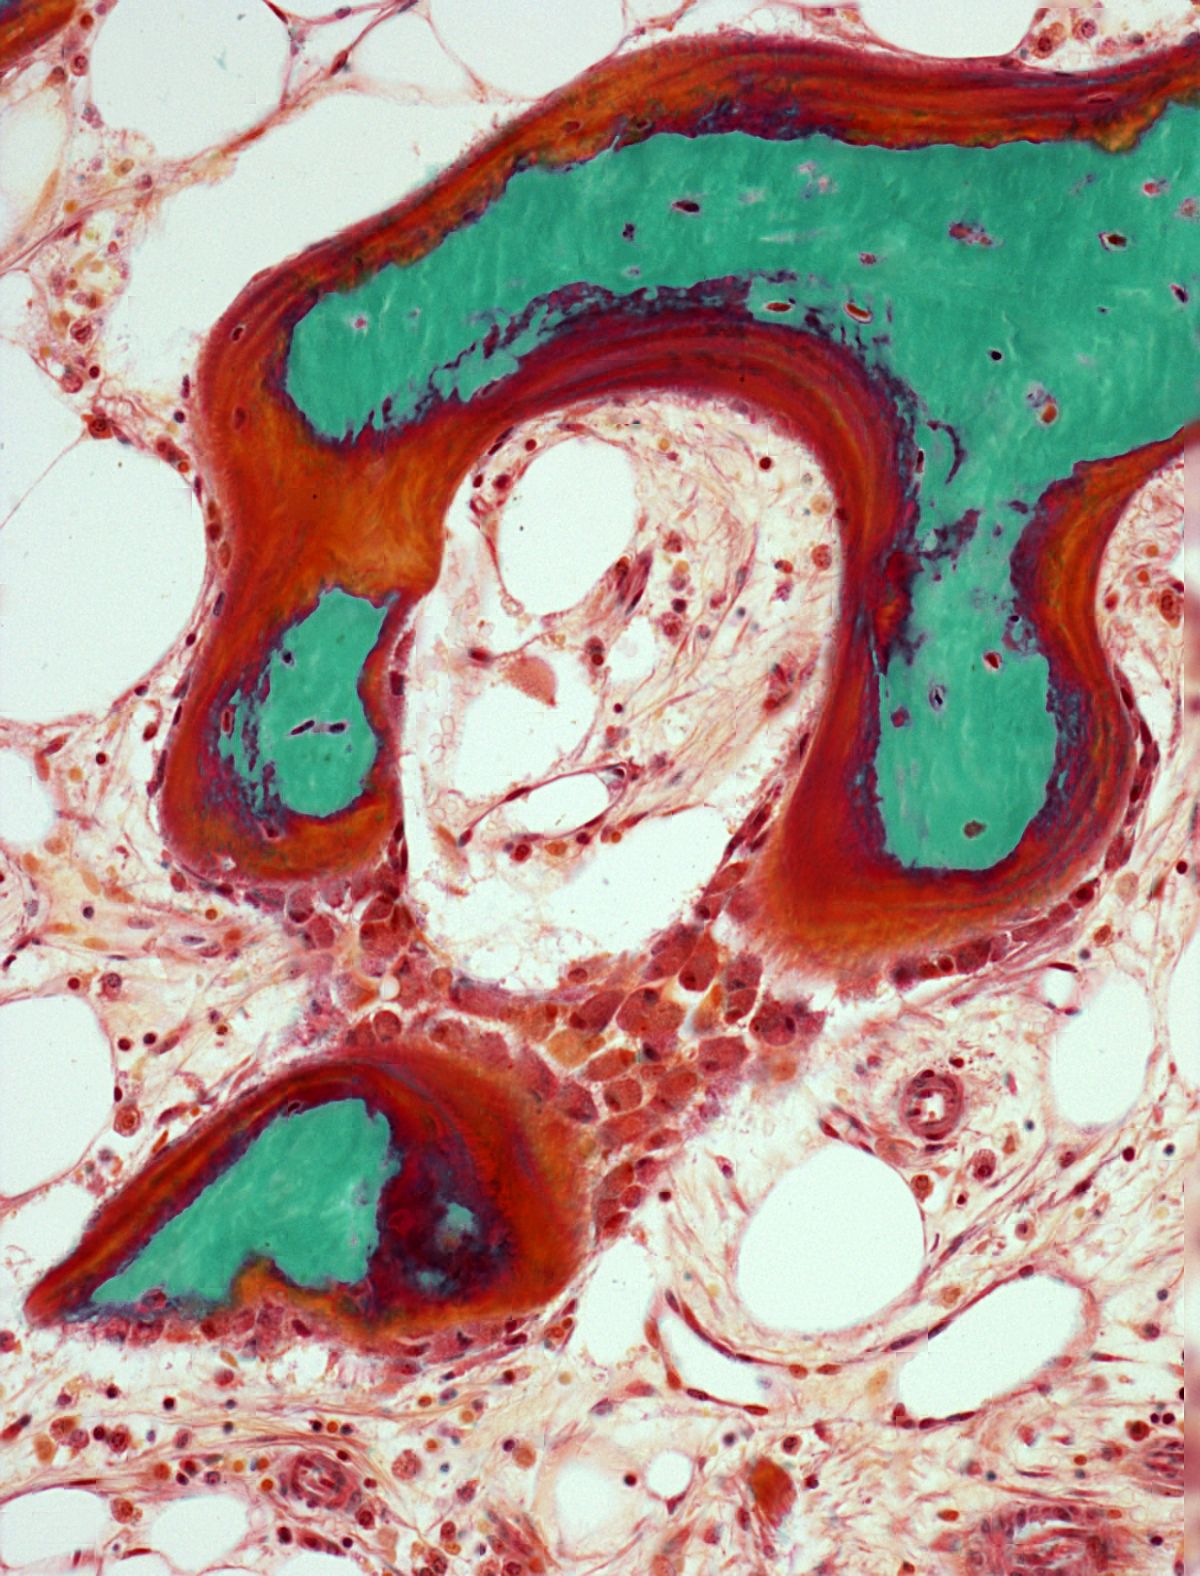

JPROUXV